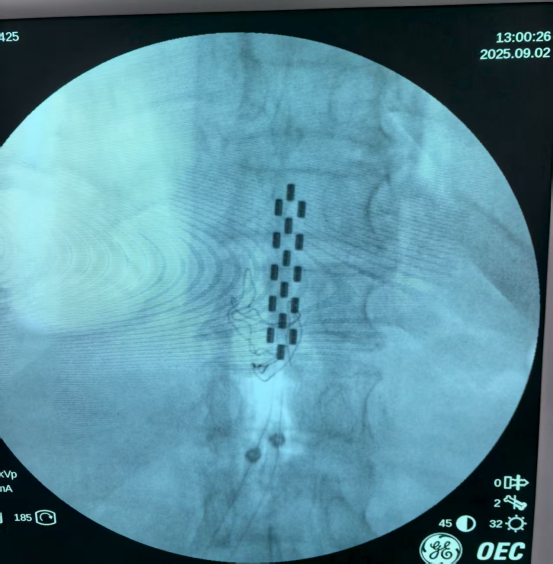

陈伟明主任团队为患者成功实施了脊髓电刺激电极植入术。次日启动设备,疗效立竿见影——患者右下肢疼痛显著缓解,左下肢麻木感消失,更令人欣喜的是,患者双下肢血运同步改善,皮肤温度明显回升。